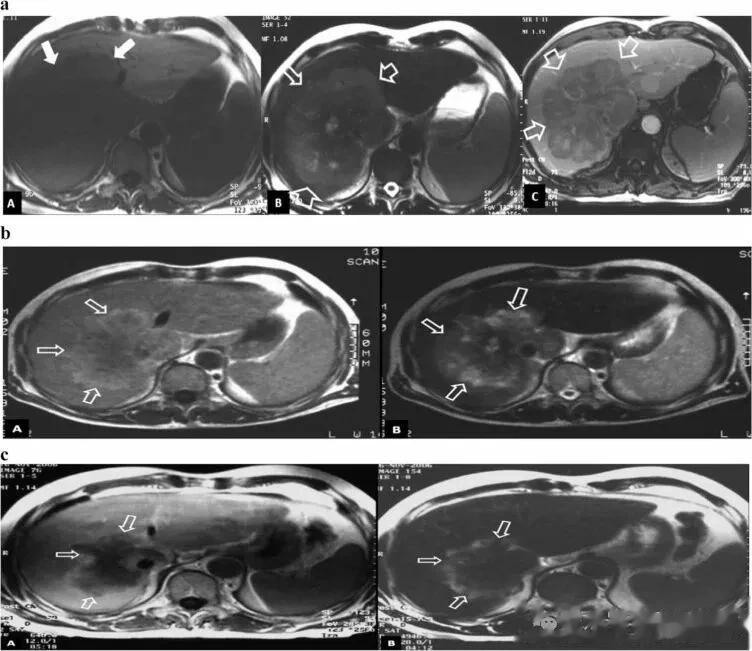

图为肝细胞癌患者

(a)接种前影像学研究。T1-w(A)、T2-w(B)和增强 T1-w(C)轴向磁共振 (MR) 图像显示肝肿瘤的初始大小(箭头)。

(b)6 个月的影像学随访研究显示 T1-w(A)和 T2-w(B)轴向 MR 图像上的病变尺寸均缩小(箭头)。

(c)10 个月的影像学随访研究显示 T1-w(A)和 T2-w(B)轴向 MR 图像上的病变尺寸进一步缩小(箭头)。